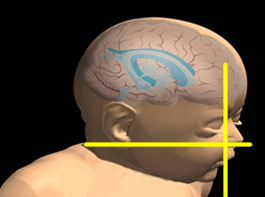

Above. Note the 3 reference planes for a 3-D sample volume.

As noted previously, increased detection is possible with 3-D which includes the usual surface rendering and the orthogonal display permitting visualization in the three reference planes: sagittal, transverse, and coronal. The transverse plane can identify the alveolus and palate by visualizing the front toot buds and alveolar ridge. When the volume is slightly rotated, the symmetry of the palate can be seen. [16] The surface rendering is useful in visually defining the defect.